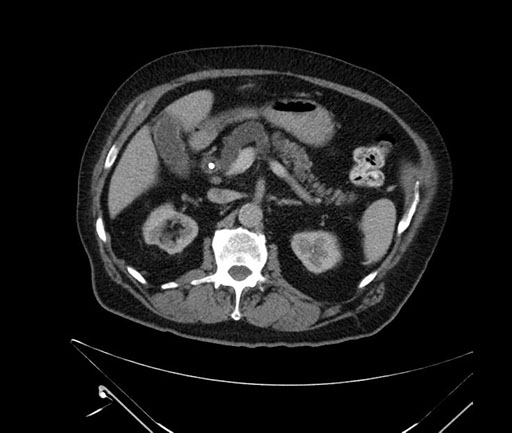

Imaging Analysis

Look through the patient's CT scan to identify any areas of concern for the necessary procedure.

Based on your CT findings, which issue(s) would give reason for "planned slowing down moment(s)" in this case?